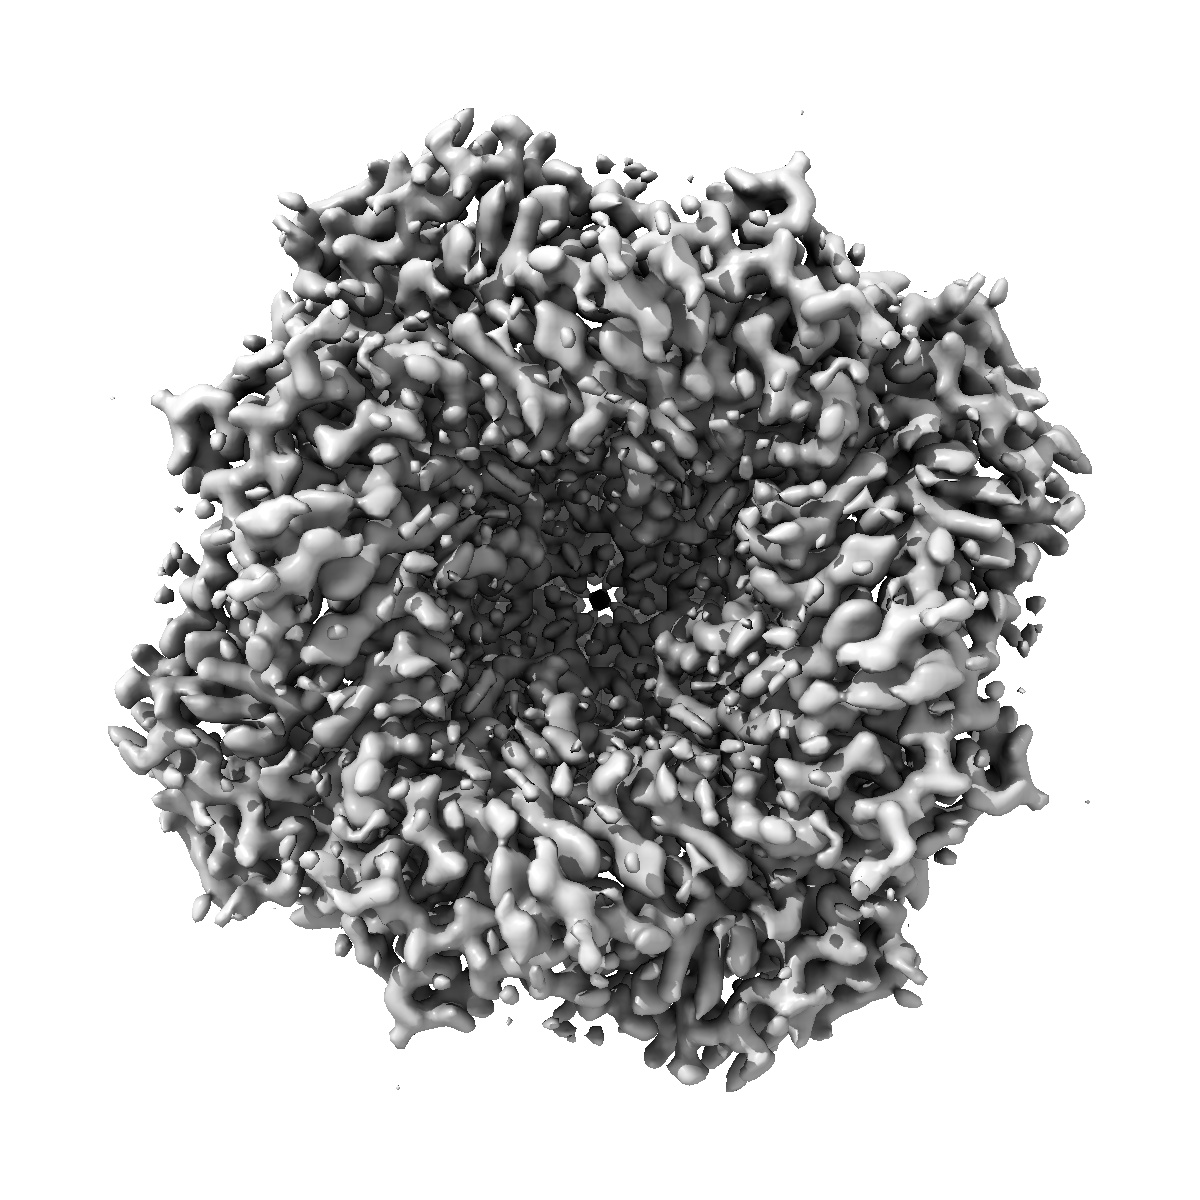

TRPML1 in complex with compound 8

Single-particle2.2 Å

Sample: Mucolipin-1

High throughput cryo-EM provides structural understanding for modulators of the lysosomal ion channel TRPML1.

(2025) Structure , 33 , 1374 - 1385.e7